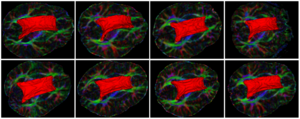

Seeing More by Showing Less: Orientation-Dependent Transparency Rendering for Fiber Tractography Visualization

Publication: PLoS One. 2015 Oct 7;10(10):e0139434. PMID: 26444010 | PDF Authors: Tax CM, Chamberland M, van Stralen M, Viergever MA, Whittingstall K, Fortin D, Descoteaux M, Leemans A. Institution: Image Sciences Institute, University Medical Center Utrecht, Utrecht, The Netherlands. Background/Purpose: Fiber tractography plays an important role in exploring the architectural organization of fiber trajectories, both in fundamental neuroscience and in clinical applications. With the advent of diffusion MRI (dMRI) approaches that can also model "crossing fibers", the complexity of the fiber network as reconstructed with tractography has increased tremendously. Many pathways interdigitate and overlap, which hampers an unequivocal 3D visualization of the network and impedes an efficient study of its organization. We propose a novel fiber tractography visualization approach that interactively and selectively adapts the transparency rendering of fiber trajectories as a function of their orientation to enhance the visibility of the spatial context. More specifically, pathways that are oriented (locally or globally) along a user-specified opacity axis can be made more transparent or opaque. This substantially improves the 3D visualization of the fiber network and the exploration of tissue configurations that would otherwise be largely covered by other pathways. We present examples of fiber bundle extraction and neurosurgical planning cases where the added benefit of our new visualization scheme is demonstrated over conventional fiber visualization approaches. Funding:

|